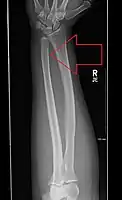

- Galeazzi facture - not a fracture of the ulna but a displaced fracture of the radius accompanied by a dislocation of the ulna at the wrist, where the radius and ulna come together.[3]

Galeazzi facture (displaced fracture of the radius) -